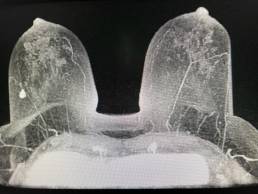

69-year-old patient, screening mammogram.

MammoScreen points to an increased opacity at the union of the outer quadrants of the right breast with a red flag (MammoScreen Score 9).

The lesion was already present on the 2019 exam and a spot compression was made.

An additional ultrasound was performed in 2021 and did not find any suspicious lesions.

Since there is nevertheless a red flag, a breast MRI is requested and finds a suspicious superior-external lesion.

Biopsy results: infiltrating adenocarcinoma associated with intracanal carcinoma..